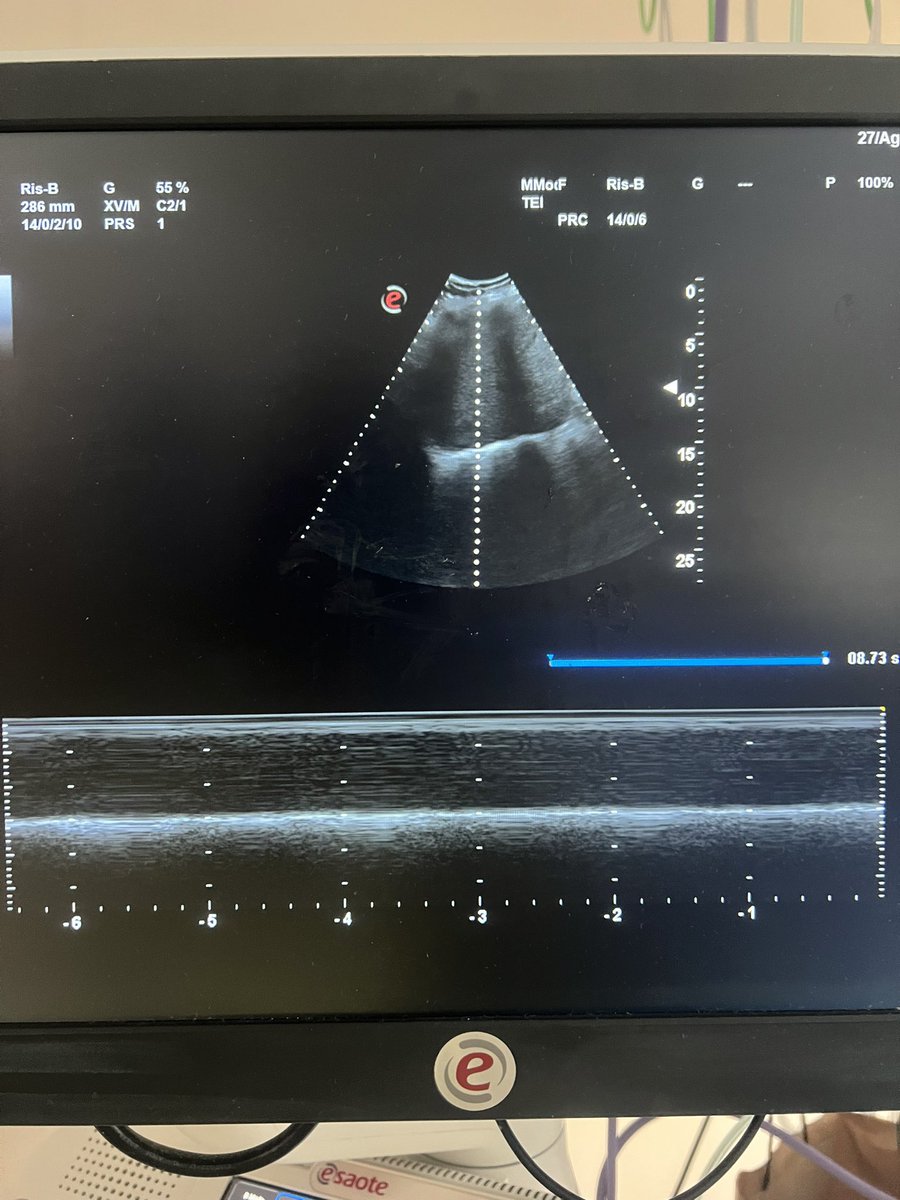

Unilateral Diaphragmatic Dysfunction secondary to phrenic nerve compression from intrathoracic mass #FOAMed #foam #MedTwitter #ultrasound